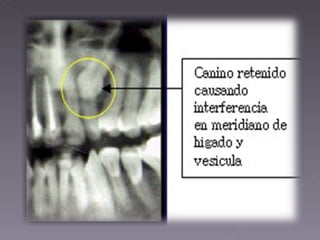

Se ha demostrado con estudios que las muelas del juicio tienen relación con casi todos los órganos del cuerpo. Las cordales retenidas pueden producir tartamudez, epilepsia, dolores articulares,  de cabeza, problemas en el corazón, deficiencia de calcio y calambres musculares, entre otros. De igual manera las otras piezas incluidas pueden ocasionar un desequilibrio de la fuerza vital, ya que impide el flujo normal de la energía a través del meridiano poniendo en riesgo su salud.

Se ha demostradocon estudios que las muelas del juicio tienen relación con casi todos los órganos del cuerpo. Las cordales retenidas pueden producir tartamudez, epilepsia, dolores articulares,  de cabeza, problemas en el corazón, deficiencia de calcio y calambres musculares, entre otros. De igual manera las otras piezas incluidas pueden ocasionar un desequilibrio de la fuerza vital, ya que impide el flujo normal de la energía a través del meridiano poniendo en riesgo su salud.